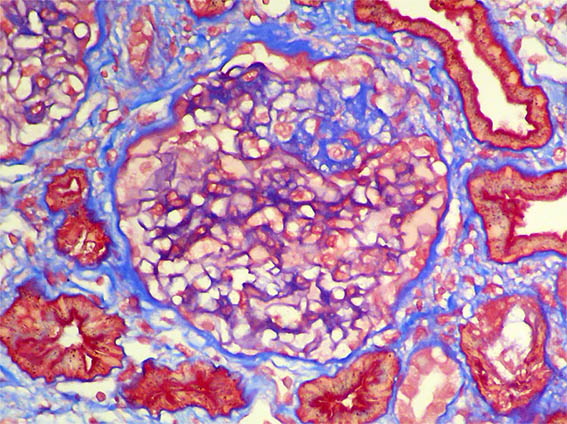

Figure 5. Masson's trichrome stain, X400.